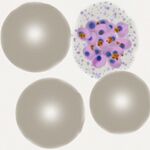

| Plasmodium falciparum |

Summary

- Small and fine ring forms, look for typical forms accolé, multiple parasites per cell, double dot

- Characteristic Maurer's dots and clefts in late trophozoites

- The irregular and "tatty" schizonts very rarely seen in blood unless severe infection

- Characteristic elongated (often curved) 'banana' gametocytes